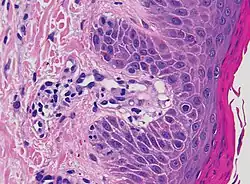

| Lichen planus | Irregular epidermal hyperplasia with a jagged “sawtooth” appearance, compact hyperkeratosis or orthokeratosis, foci of wedge-shaped hypergranulosis, basilar vacuolar degeneration, slight spongiosis in the spinous layer, and squamatization. The dermal papillae between the elongated rete ridges are frequently dome shaped. Necrotic keratinocytes can be observed in the basal layer of the epidermis and at the dermal-epidermal junction. Eosinophilic remnants of anucleate apoptotic basal cells may also be found in the dermis and are referred to as “colloid or civatte bodies”. Whickham striae are usually seen in the areas of hypergranulosis. Vacuolar degeneration at the basal layer may be noted leading to focal subepidermal clefts (Max Joseph spaces). Squamatization occurs as a result of maturation and flattening of cells in the basal layer. It happens in areas of marked hypergranulosis with prominence of the sawtooth pattern of rete ridges. Wedge-shaped hypergranulosis can occur in the eccrine ducts (acrosyringia) or hair follicles (acrotrichia). In the hypertrophic subtype, the associated hyperkeratosis, parakeratosis, hypergranulosis, papillomatosis, acanthosis, and hyperplasia markedly increased with thicker collagen bundles forming in the dermis. Moreover, the rete ridges are more elongated and rounded as opposed to the typical sawtooth pattern. In atrophic LP, loss of the rete ridges and dermal fibrosis is prominent. In vesiculobullous LP, the disease progression is quicker. Hence, some of the distinctive features such as hyperkeratosis, hypergranulosis, or dense lymphocytic dermal-epidermal infiltrate may not be present. LP lesion may resolve with residual hyperpigmentation caused by a persistent increase in the number of melanophages in the papillary dermis.[9] | ![]() |

|

| Lichenoid drug reaction |

Can virtually be indistinguishable from cutaneous LP both clinically and histopathologically.

![]() |